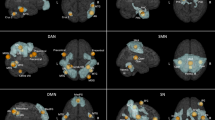

Neuroimaging studies in humans and non-human primates have provided insight into the systems-level disturbances that are responsible for dystonia. These indicate a central role for abnormal plasticity, affecting the sensorimotor system, leading to distortion of sensory fields in the sensorimotor cortex and abnormal signalling in the basal ganglia.

Eidelberg, D. et al. Functional brain networks in DYT1 dystonia. Ann. Neurol. 44, 303–312 (1998). This fMRI study established dystonia as a network disorder and set the design and interpretation of future functional imaging studies, highlighting that dystonia patients, even at rest, do not have the same functional neural baseline as healthy controls. It provided a means to distinguish the brain regions involved in dystonic symptoms themselves (movement-related regions) from those which may underlie more fundamental endophenotypic traits of the disorder (movement-free regions).

Ceballos-Baumann, A. O. et al. Overactive prefrontal and underactive motor cortical areas in idiopathic dystonia. Ann. Neurol. 37, 363–372 (1995).

Ibanez, V., Sadato, N., Karp, B., Deiber, M. P. & Hallett, M. Deficient activation of the motor cortical network in patients with writer's cramp. Neurology 53, 96–105 (1999).

Dresel, C., Haslinger, B., Castrop, F., Wohlschlaeger, A. M. & Ceballos-Baumann, A. O. Silent event-related fMRI reveals deficient motor and enhanced somatosensory activation in orofacial dystonia. Brain 129, 36–46 (2006).

Blood, A. J. et al. Basal ganglia activity remains elevated after movement in focal hand dystonia. Ann. Neurol. 55, 744–748 (2004).

Pujol, J. et al. Brain cortical activation during guitar-induced hand dystonia studied by functional MRI. Neuroimage 12, 257–267 (2000).